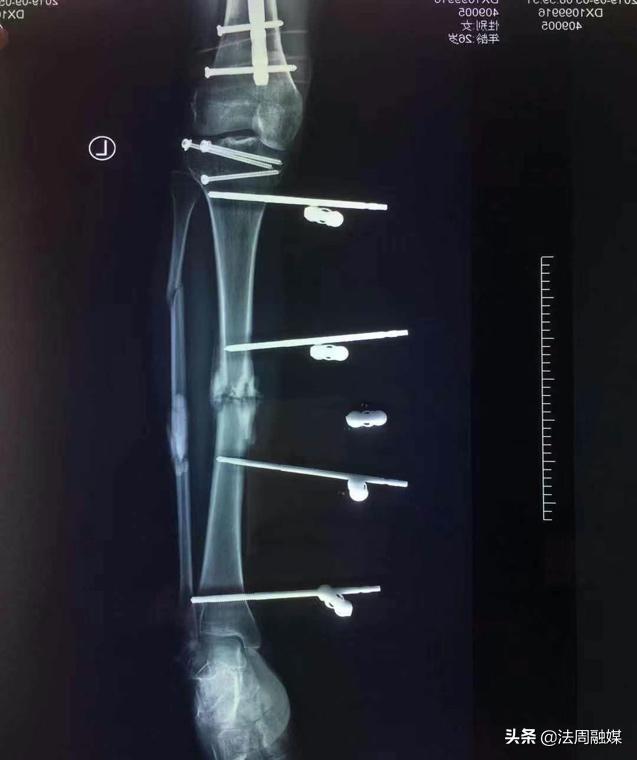

由于损伤严重,骨缺损,小文在后期康复中,骨折部位愈合不良并出现“马蹄内翻足”,站立行走困难。此时,肖群飞想出了奇招,去除外固定架,闭合扩髓达到植骨目的并髓内钉固定促进骨折愈合,再利用“克氏针配合橡皮筋”持续牵引纠正马蹄足内翻。后来,经过医生的精准治疗和自身不断的康复锻炼,小文逐渐站立起来,筑立起了明日美好的生活!

“克氏针配合橡皮筋”持续牵引纠正马蹄内翻足,可避免繁杂的畸形松解手术,使患者以最小代价得到最好的康复。

外固定支架+抗生素骨水泥+VSD治疗严重胫腓骨开放性骨折,相对于传统的内外固定技术有着较大的优势,外固定支架治疗原则“简单、迅速,有效”,固定可靠,软组织干预少,安装快捷,有利于损伤控制。外固定支架良好的架空技术可以在不影响骨折端的情况下同时对软组织创面进行观察、换药、植皮等手术处理。VSD(负压封闭引流技术)引流通畅,可以保证创面清洁,阻止感染的扩散,且改善局部微循环,促进创面愈合,减少天天换药给患者带来的痛苦,能让患者降低医疗费用。抗生素骨水泥能有效预防及治疗感染,对于骨折后期愈合不良者,闭合扩髓交锁钉内固定,既能免除取髂骨带来的新的痛苦,又促进了骨折愈合及康复。(来源:常德市第一中医医院)